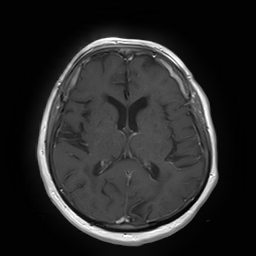

(a) Guide 𝑮𝑮\boldsymbol{G}

Refer to caption

(b) Input 𝑰𝑰\boldsymbol{I}

(c) Guidance map 𝑴𝑴\boldsymbol{M}

(d) Prediction 𝑷𝑷\boldsymbol{P}

(e) Ground truth

Figure 2: Inputs and outputs of the guided filtering pipeline based on the WDSR network. T1 & T2 MRI pairs (a)-(e) and CT & MRI projection images (f)-(j).